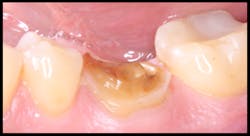

This is a case report of a tooth that was previously restored using a direct technique and a glass ionomer restoration. When the restoration failed, it completely debonded from the tooth surface, and minimal tooth structure remained (figures 1 and 2). When treatment options were discussed with the patient, he refused all traditional restorative therapies. In fact, he refused any preparation of his remaining tooth structure and requested that the tooth be restored with a direct glass ionomer restoration.

Figure 1: Lateral view at initial presentation

Figure 2: Occlusal view at initial presentation